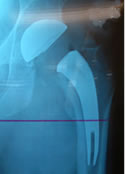

| The ARCTM Stem with modular trial neck. |